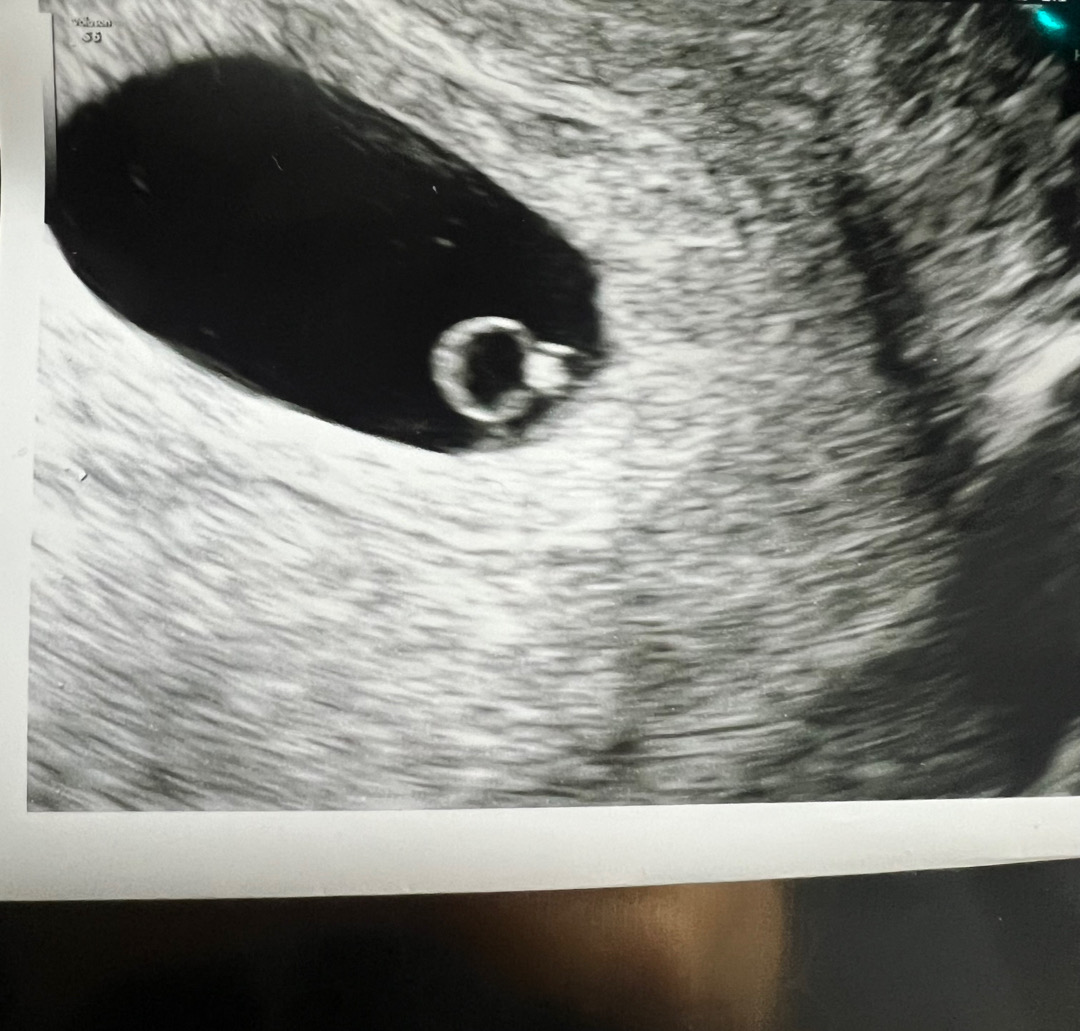

초음파로 심장박도 재고 왔어요!

6주1일이라 심소는 이르다고 못듣고 초음파로 85인거 확인하고 왔네요 제대로 다이아반지라서 넘나 신기해용